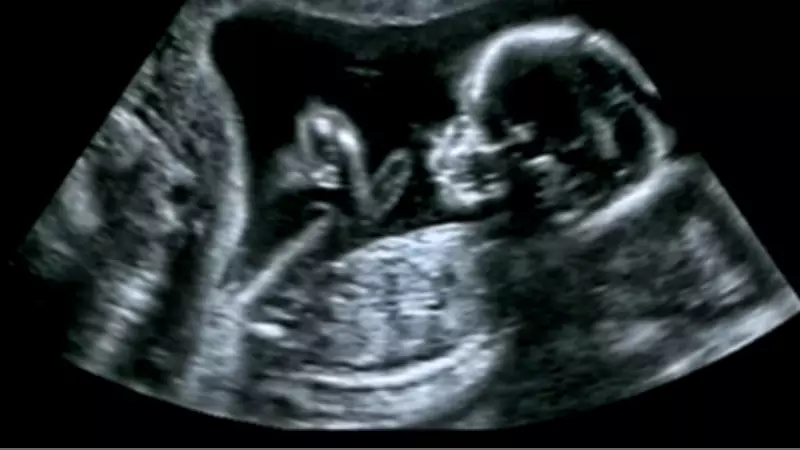

Kalp ve Damar Sağlığı Anne Karnında Başlıyor: Uzman İsimden Hayati Açıklamalar

Sağlık Bilimleri Üniversitesi (SBÜ) Antalya Eğitim ve Araştırma Hastanesi Kalp Damar Cerrahisi Ana Bilim Dalı Öğretim Üyesi Prof. Dr. Ali Ümit Yener, kalp ve damar sağlığının anne karnında başlayıp ölüme kadar devam eden kritik bir süreç olduğunu belirtti. Yener, bu konuda yaptığı açıklamalarla rutin kontrollerin hayat kurtarıcı rolüne dikkat çekti.